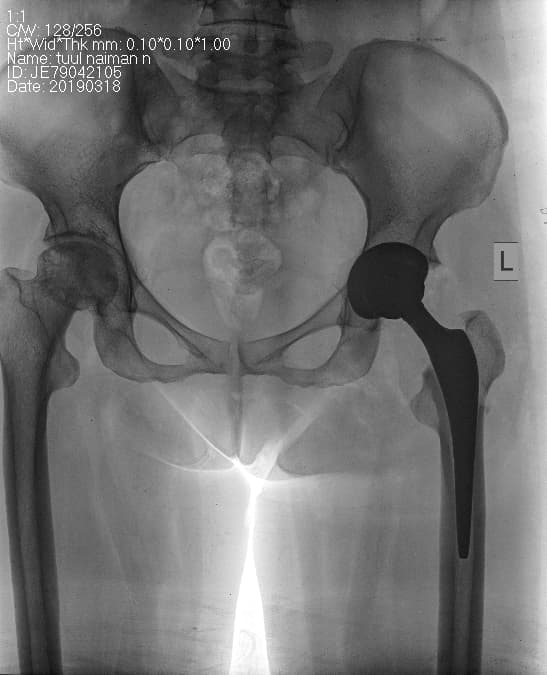

Мэс заслын өмнөх болон дараах рентген зураг

Дунд чөмөгний дээд хэсгийн /проксималь/ хавдар

Дунд чөмөгний проксималь буюу дээд хэсгийг хамарсан яс, зөөлөн эдийн гаралтай хавдрын улмаас түнхний үе, дунд чөмөгний дээд хэсгийг бүхлээр нь солих (мөч хадгалах мэс засал) мэс заслын эмчилгээг хийнэ.